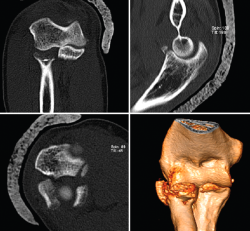

Este patrón de inestabilidad compleja de codo se caracteriza por una luxación posterior de codo asociada a 3 lesiones principales (Figura 14):

• Fractura de la cabeza del radio.

• Rotura del LCL.

• Fractura de la coronoides.

Figura 14. Tríada terrible de codo derecho donde puede apreciarse en las imágenes de tomografía computarizada la fractura de la cabeza del radio, la fractura de la coronoides y la subluxación posterolateral de la ulnohumeral.